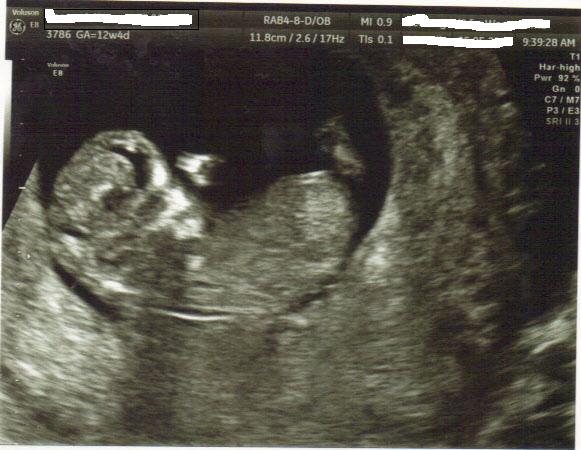

Had my 12w4d ultrasound last friday. Here is the picture - not much to go on though. I asked the sonographer about gender and he was a real arse, so think he went nowhere near the nub on purpose! Anyway, guess away just for fun.

I tried to take some screen shots from the video, but they come out way too big to post here.